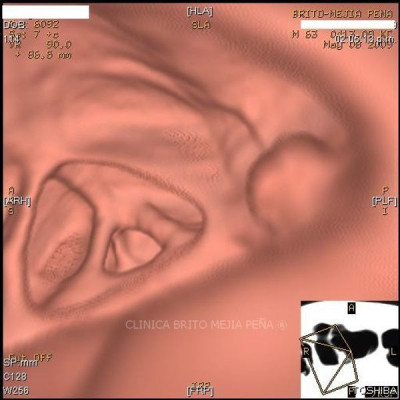

Colonoscopía virtual